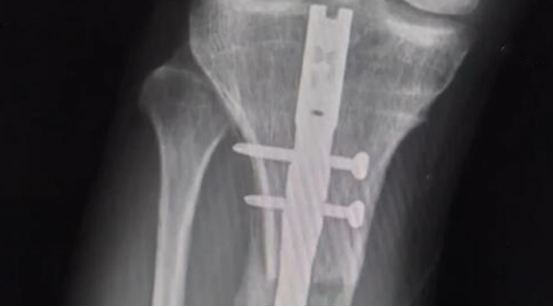

在做手术之前,医生给他进行全面的检查,最终确定术后会增加7.5厘米。

2014年9月24日,李亚诺怀着重生的心,进入了手术室。

这场手术进行了好几个小时,手术结束后,李亚诺被平安地推了出来,

医生告诉他的父母,手术很成功,

如果术后恢复得不错,明年他的身高就能达到174厘米。

在复查的时候,医生告诉他们李亚诺还要做一次手术,这次手术做完后,应该会恢复的不错。

就这样,20岁的李亚诺再次躺进手术室,这一次手术过程进展得很顺利,

然而术后李亚诺的恢复却不为理想。

在拆掉腿部支架后,他的腿部肌肉出现了病变,他再也不能像正常人一样走路了。

更遗憾的是,他有时候连站都站不起来。

慢慢的,他的腿部出现变形,脚部也出现问题,总之他的恢复很糟糕。